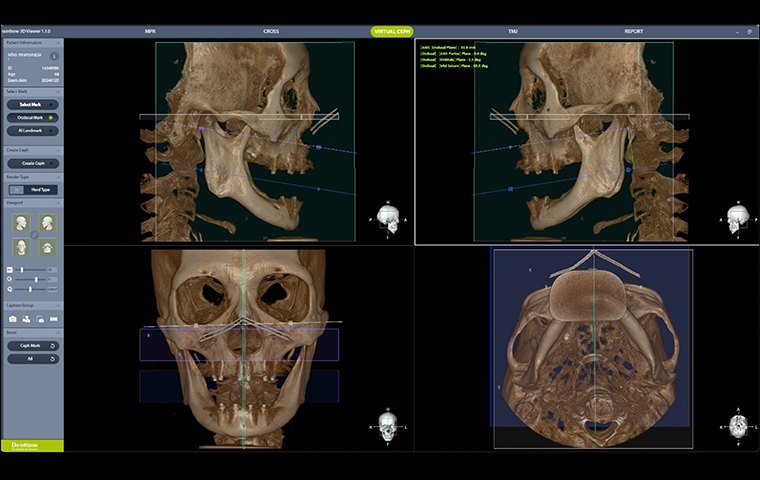

TMJ Disorders

TMJ Disorders and Splints

Dr. Samuel S.Y. Kim

Specialist TMJ surgeon

TMJ Disorders

TMJ Disorders and Splints

Dr. Samuel S.Y. Kim

Specialist TMJ surgeon

| 16:00 – 17:00 |

TMJ Disorders

Dr. Samuel S.Y. Kim

|

TMJ Disorders and Splints |

| 16:00 – 17:00 |

TMJ Disorders

Dr. Samuel S.Y. Kim

|

TMJ Disorders and Splints |